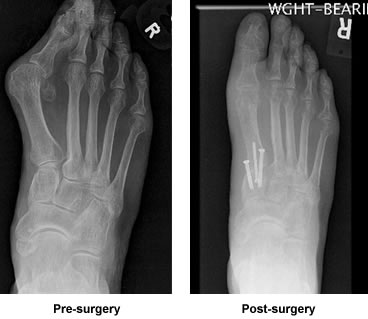

Fast forward to 2016, the pain never really went away and at times the nerve pain would bring me to my knees. Also as a result of the damage, my foot was deformed. My big tow hung a right turn over my other toes. Finding shoes that were comfortable was not easy. I lived in sneakers. Finally after thinking I was going to have to live with this my entire life, my primary care physician said enough was enough and referred me to Dr. Leavitt.

My first appointment with him was great. He looked at my foot like a kid in a candy store. The challenge was too much to pass up. From then on I felt sure there was hope to have a normal looking foot without constant nerve pain. Dr. Leavitt was so amazing. He gave my life back to me. He was never too busy to answer any of my questions or concerns. He has a great sense of humor and immediately makes you feel comfortable. The day of the operation different problems arose, but he quickly solved them and got down to business. It was a long operation and my wife was a nervous wreck. After the operation, Dr. Leavitt went out to the waiting room and gave my wife an x-ray of my new and improved right foot.